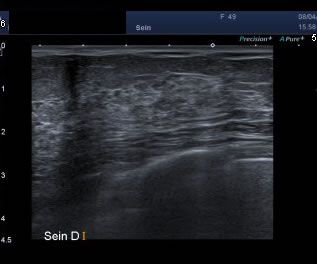

-L'échographie est souvent réalisé au décours d'une mammographie ; elle permet bien souvent de visualiser la glande mammaire, quand celle-ci est dense et moins analysable en mammographie.

Echographie mammaire

Un examen échographique qui permet, dans la continuité de votre examen , de mener un diagnostic précis en sénologie